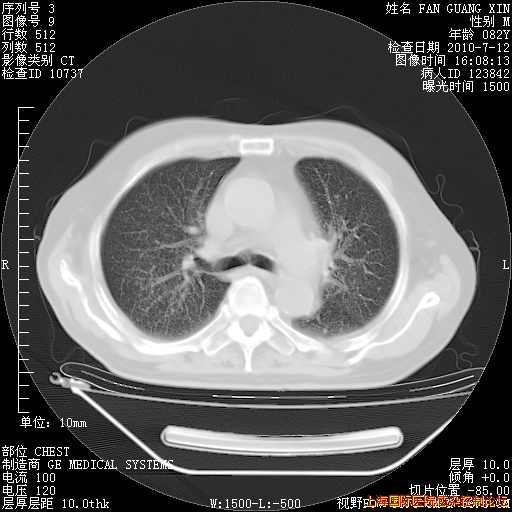

今天复查CT

今天CT

整整相隔30天的肺部CT好像有所好转啊。甲强龙减量第3天,需要观察体温。

海管,自昨日你和我通完话后,不知您岳父消化道症状有无缓解?体温怎样?阅读7.12日胸部ct,个人认为目前激素治疗是有效的,甲强龙减量是适宜的。因在抗痨治疗,需密切观察肝功、肾功能和血常规。不过,老年、长期住院和大量使用激素,很担心菌群失调发生